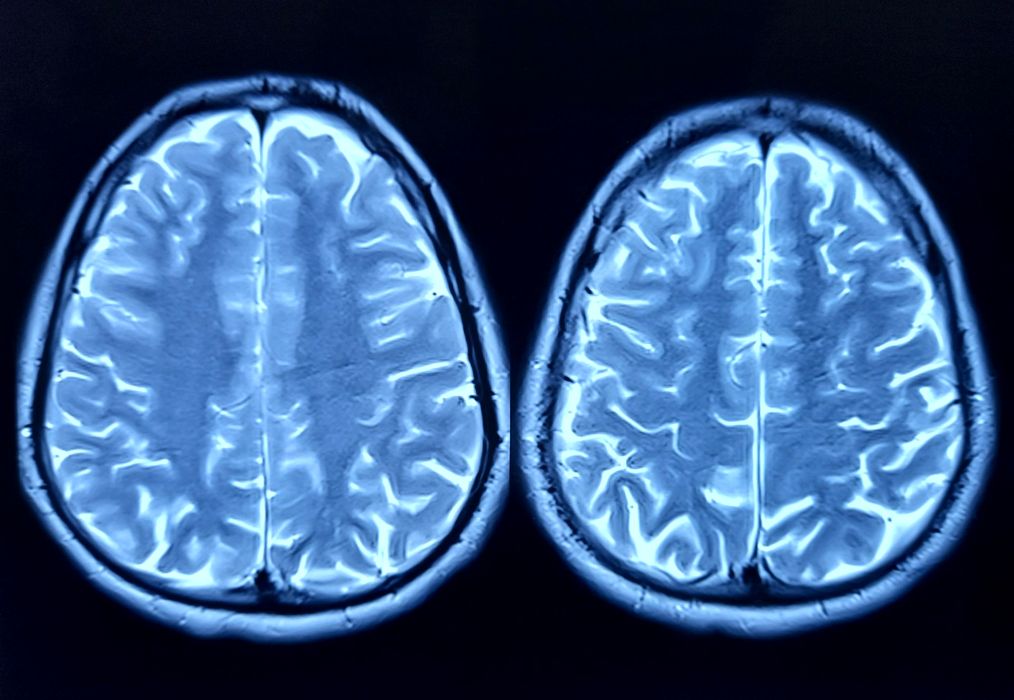

Câtă energie consumă creierul uman? Vom putea construi vreodată un computer la fel de eficient?

Câtă energie consumă creierul uman? În prezent, computerele au devenit incredibil de puternice. Pot calcula trilioane de zecimale ale lui pi sau pot influența comportamentele umane, însă costul este uriaș: impact asupra mediului, consum masiv […]